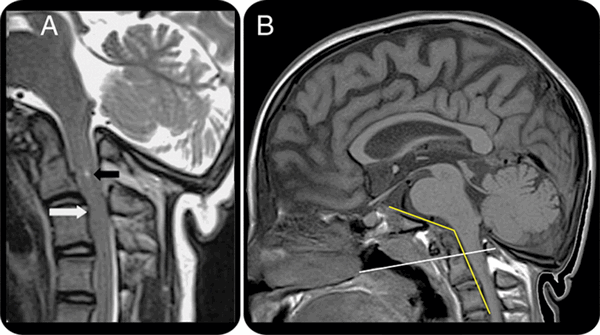

Опухоль краниовертебральной области (обозначена стрелкой)

На МРТ краниовертебрального перехода − платибазия и базилярная импрессия при несовершенном остеогенезе